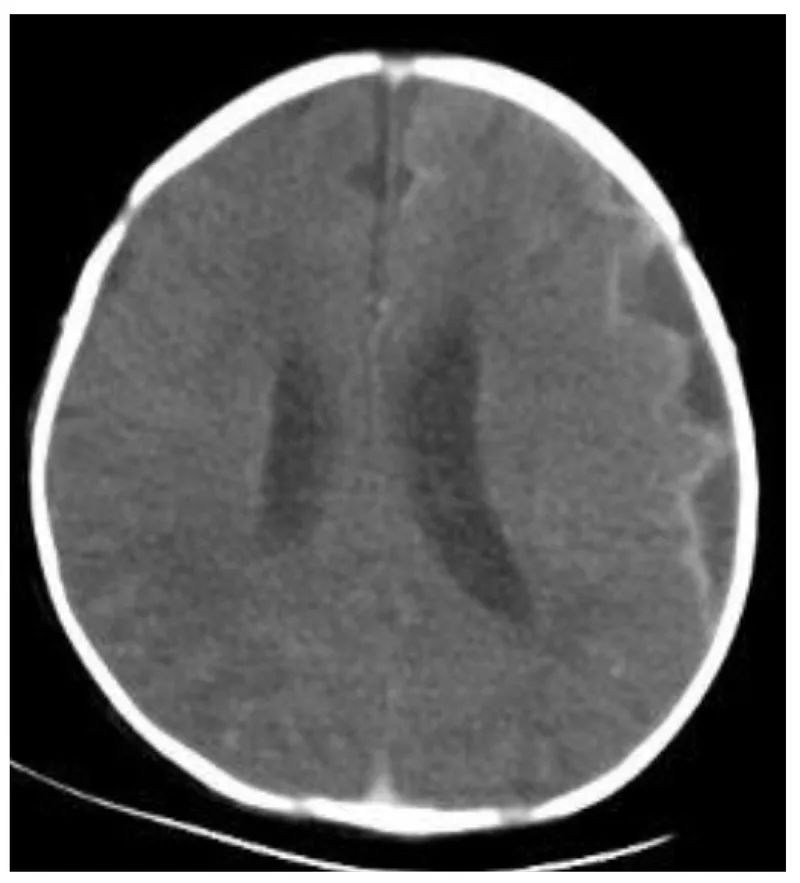

- Acute: SIADH, subdural effusion/empyema, ventriculitis, brain abscess, communicating hydrocephalus.